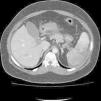

Con enoxaparina sódica, nutrición parenteral y perfusión de metamizol magnésico, la paciente se encuentra asintomática. Al octavo día de ingreso, dolor abdominal difuso, episodio de melenas (200cc), hemoglobina 7,7g/dl y hematocrito 25%, se transfunden 2 concentrados de hematíes y se consulta con radiología intervencionista que tras revisar imágenes de angio-TC previas, decide por abordaje femoral, cateterismo de arteria mesentérica superior, dejando catéter en el tronco principal del vaso, para perfusión de urocinasa 100.000UI en 500cc de suero fisiológico a 100ml/h. A los 3 días del tratamiento fibrinolítico, se realiza estudio angiográfico con fases tardías, apreciándose repermeabilización parcial de la vena porta (fig. 2). Se retira catéter femoral y se reinicia anticoagulación.